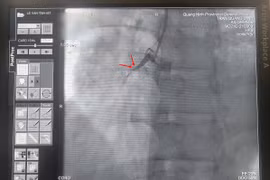

Cứu bệnh nhân tắc nghẽn van tim bằng tiêu sợi huyết

Lần đầu tiên bệnh viện Đa khoa Phú Thọ đã ứng dụng công nghệ tiêu sợi huyết để cứu sống bệnh nhân (BN) bị tắc nghẽn van tim (kẹt van) nặng, phù phổi cấp, huyết áp tụt sốc tim…